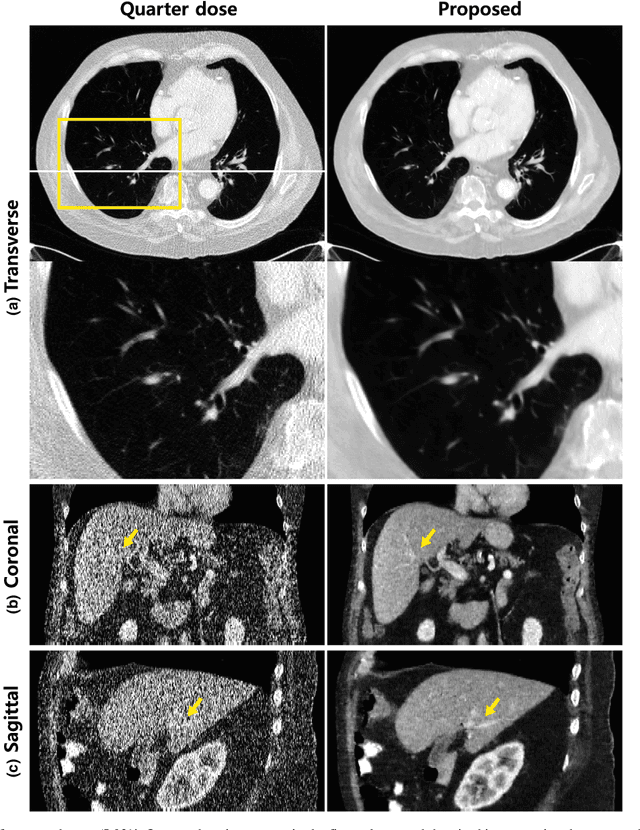

Abstract:Due to the potential risk of inducing cancers, radiation dose of X-ray CT should be reduced for routine patient scanning. However, in low-dose X-ray CT, severe artifacts usually occur due to photon starvation, beamhardening, etc, which decrease the reliability of diagnosis. Thus, high quality reconstruction from low-dose X-ray CT data has become one of the important research topics in CT community. Conventional model-based denoising approaches are, however, computationally very expensive, and image domain denoising approaches hardly deal with CT specific noise patterns. To address these issues, we propose an algorithm using a deep convolutional neural network (CNN), which is applied to wavelet transform coefficients of low-dose CT images. Specifically, by using a directional wavelet transform for extracting directional component of artifacts and exploiting the intra- and inter-band correlations, our deep network can effectively suppress CT specific noises. Moreover, our CNN is designed to have various types of residual learning architecture for faster network training and better denoising. Experimental results confirm that the proposed algorithm effectively removes complex noise patterns of CT images, originated from the reduced X-ray dose. In addition, we show that wavelet domain CNN is efficient in removing the noises from low-dose CT compared to an image domain CNN. Our results were rigorously evaluated by several radiologists and won the second place award in 2016 AAPM Low-Dose CT Grand Challenge. To the best of our knowledge, this work is the first deep learning architecture for low-dose CT reconstruction that has been rigorously evaluated and proven for its efficacy.